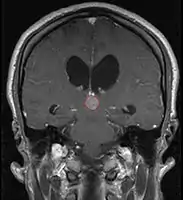

< Radiation Oncology < CNS

Pineal Gland Tumors

Clinical Presentation

• Determined by the spatial anatomy and direction of growth

• Obstruction of aquaduct: hydrocephalus presenting as headaches, nausea, vomiting

• Compromise of superior colliculus: vertical gaze palsy, pupillary and oculomotor nerve paresis (Parinaud syndrome)

• Progressive growth: cranial nerve neuropathies, hypothalamic dysfunction